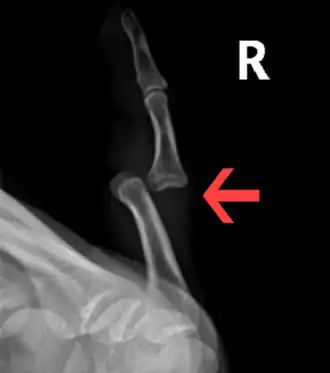

Radiograph of right fifth phalanx bone dislocation -